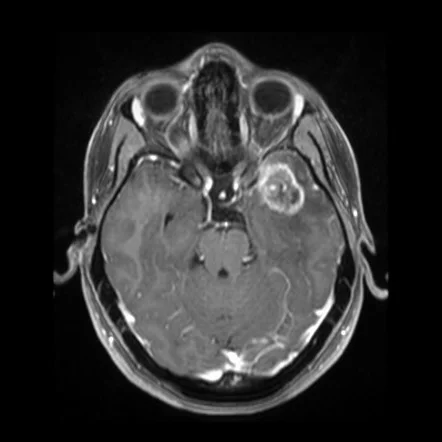

Η μαγνητική τομογραφία (MRI) με σκιαγραφικό είναι η εξέταση αναφοράς. Ορισμένα απεικονιστικά “μοτίβα” είναι ενδεικτικά, αλλά η οριστική διάγνωση παραμένει ιστολογική.

Γενικά: οι βλάβες είναι συχνά καλά οριοθετημένες και φλοιϊκές/επιφανειακές.

- PXA: συχνά κυστική βλάβη με τοιχωματικό οζίδιο, ποικίλη ενίσχυση, συχνά επιφανειακή/φλοιϊκή.

- DNET: πολυοζώδης εικόνα, μικρή ή καμία ενίσχυση, συνήθως χωρίς έντονο οίδημα ή φαινόμενα μάζας.

- Γαγγλιογλοίωμα: ετερογενής, κυστικός ή/και συμπαγής όγκος, μεταβλητή ενίσχυση, συχνές επασβεστώσεις.